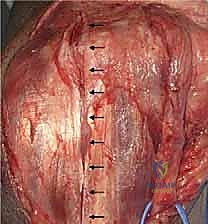

6. ربط المفصل وإغلاق الجرح

بعد جفاف الإسمنت، يتم ربط جزئي المفصل (العضد والزند) معاً بمحور معدني (Linked Prosthesis)، مما يمنع خلع المفصل مستقبلاً. يعيد الدكتور هطيف بناء الأوتار (خاصة وتر العضلة الثلاثية) بدقة متناهية، ثم يتم إغلاق الجرح تجميلياً.